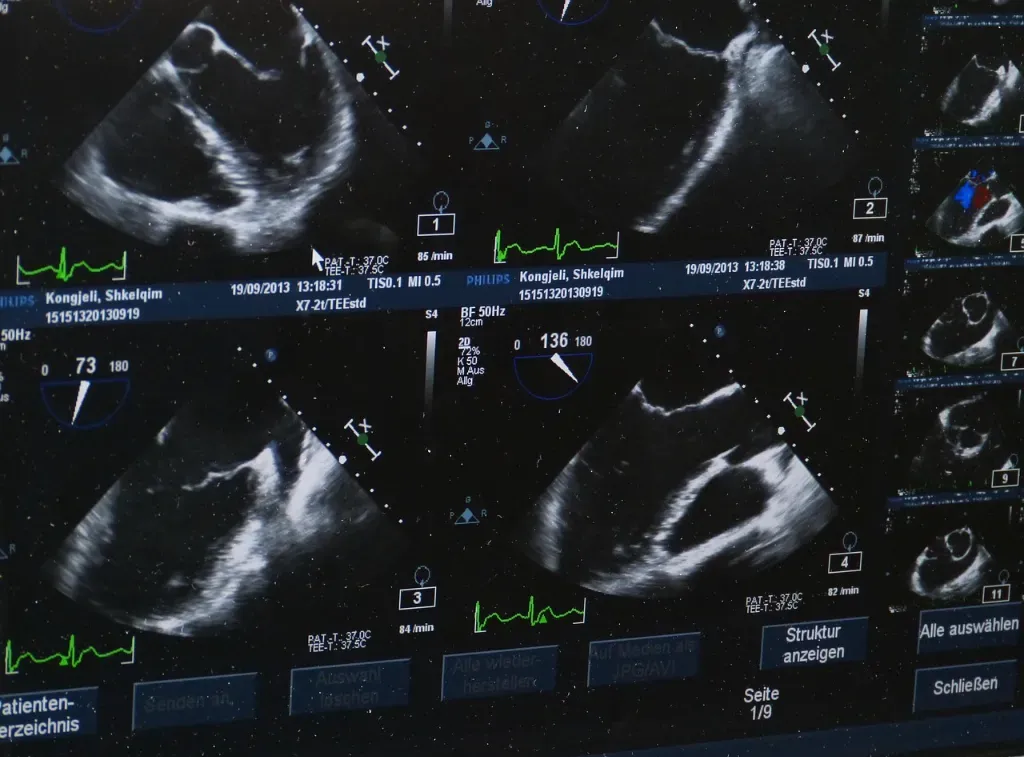

Ultrasonografia wykorzystuje fale dźwiękowe o wysokiej częstotliwości, które odbijają się od tkanek i tworzą obraz w czasie rzeczywistym. Nie ma tu promieniowania jonizującego. Dzięki temu badanie jest szeroko stosowane u kobiet młodszych, w ciąży i w okresie karmienia.

USG dobrze różnicuje zmiany lite i torbielowate, pozwala ocenić ich zarys, zawartość, unaczynienie (w trybie dopplerowskim) oraz relacje z otoczeniem. Ułatwia też precyzyjne nakłucia diagnostyczne, gdy są wskazane. To badanie operatorozależne: doświadczenie osoby wykonującej ma duży wpływ na jakość opisu. Warto też pamiętać o ograniczeniach – ultrasonografia gorzej uwidacznia zwapnienia i nie zastępuje mammografii w badaniach przesiewowych odpowiednich grup wiekowych.